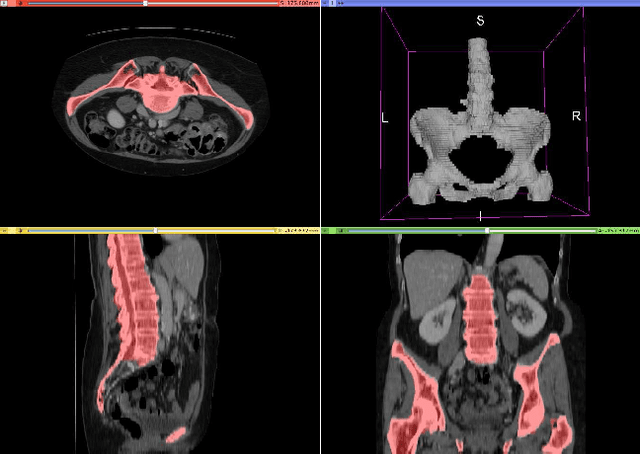

Abstract:Fully-convolutional neural networks have achieved superior performance in a variety of image segmentation tasks. However, their training requires laborious manual annotation of large datasets, as well as acceleration by parallel processors with high-bandwidth memory, such as GPUs. We show that simple models can achieve competitive accuracy for organ segmentation on CT images when trained with extensive data augmentation, which leverages existing graphics hardware to quickly apply geometric and photometric transformations to 3D image data. On 3 mm^3 CT volumes, our GPU implementation is 2.6-8X faster than a widely-used CPU version, including communication overhead. We also show how to automatically generate training labels using rudimentary morphological operations, which are efficiently computed by 3D Fourier transforms. We combined fully-automatic labels for the lungs and bone with semi-automatic ones for the liver, kidneys and bladder, to create a dataset of 130 labeled CT scans. To achieve the best results from data augmentation, our model uses the intersection-over-union (IOU) loss function, a close relative of the Dice loss. We discuss its mathematical properties and explain why it outperforms the usual weighted cross-entropy loss for unbalanced segmentation tasks. We conclude that there is no unique IOU loss function, as the naive one belongs to a broad family of functions with the same essential properties. When combining data augmentation with the IOU loss, our model achieves a Dice score of 78-92% for each organ. The trained model, code and dataset will be made publicly available, to further medical imaging research.